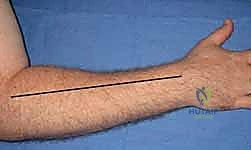

The volar approach is the cornerstone of forearm decompression. A curvilinear incision is utilized to prevent linear scar contracture across the flexion creases. The incision begins just proximal to the medial epicondyle, courses distally and radially across the antecubital fossa, extends longitudinally down the mid-volar forearm, and then curves ulnarly at the wrist to cross the wrist crease obliquely, terminating in the palm along the thenar crease.

The dissection proceeds through the subcutaneous tissues, taking meticulous care to identify and protect the palmar cutaneous branch of the median nerve at the wrist and the medial antebrachial cutaneous nerve proximally. The deep investing fascia of the superficial volar compartment is incised longitudinally.

Crucially, the surgeon must decompress the deep volar compartment. This is achieved by retracting the flexor carpi radialis radially and the flexor digitorum superficialis ulnarly, exposing the deep fascia overlying the flexor digitorum profundus and flexor pollicis longus. This deep fascia is incised entirely.

At the wrist, a formal carpal tunnel release is mandatory. The transverse carpal ligament is divided completely to decompress the median nerve. Proximally, the lacertus fibrosus (bicipital aponeurosis) must be divided to decompress the brachial artery and median nerve in the antecubital fossa. Any muscle bellies that appear pale, dusky, or non-contractile should undergo epimysiotomy (incising the epimysium directly) to further relieve localized pressure.

Dorsal Forearm Decompression

While the volar incision decompresses a significant volume, a dorsal release is frequently required, especially in severe trauma or when dorsal compartment pressures remain elevated. A straight longitudinal incision is made from the lateral epicondyle to the midline of the distal radioulnar joint.

The subcutaneous tissues are divided, protecting the superficial sensory branch of the radial nerve. The extensor retinaculum is preserved if possible to prevent bowstringing of the extensor tendons, but the fascial compartments between the extensor digitorum communis and the mobile wad are widely opened.